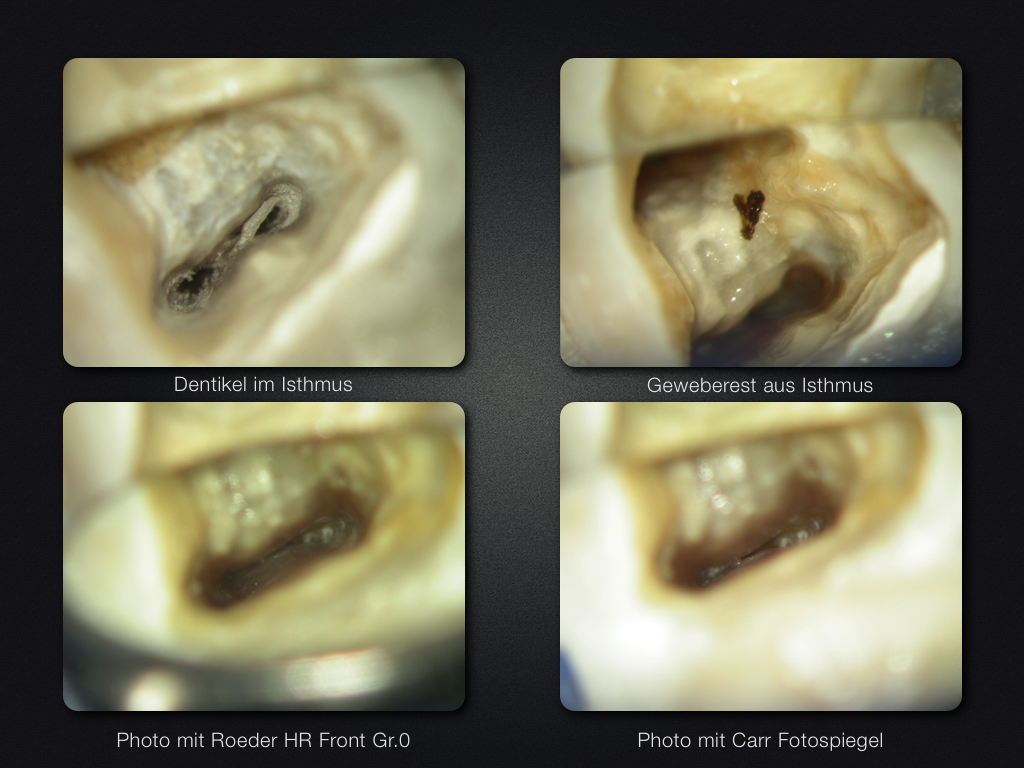

37D.007

2D vs. 3D (XXIV)